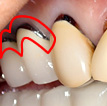

右下の図の症例では、被せ物の歯肉周辺が、うっすら黒く変色しているのが解ります。この歯には「金銀パラジウム合金」という、金属の被せ物を装着されて7年が経過しております。

溶出した「金銀パラジウム合金」が、組織や血管の中に染み込み、そこで酸化(錆びる事)して、長年の経過で黒く変色したものと考えられます。

金属溶出(メタルタトゥー)の症例